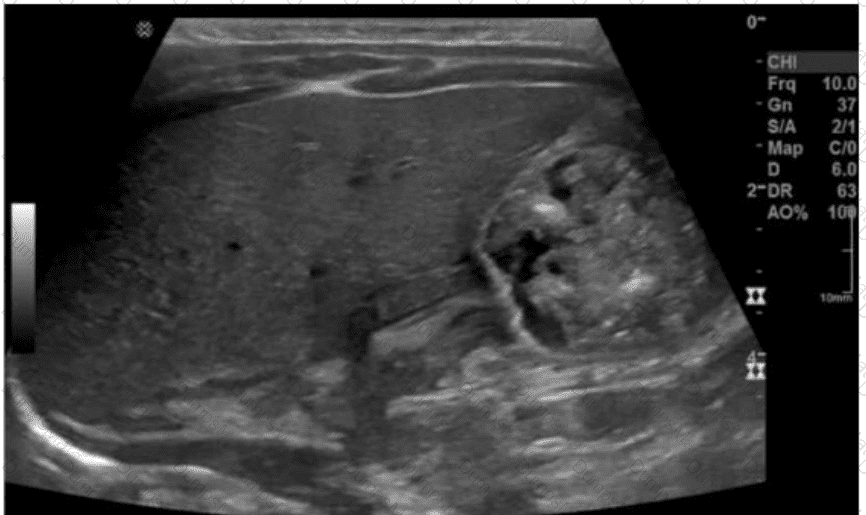

Questions 28

Which condition is most consistent with the findings in this image?

AB-Abdomen Question 28

Options:

A.

Fungal balls

B.

Renal cell carcinoma

C.

Acute pyelonephritis

D.

Medullary sponge kidney

Buy Now